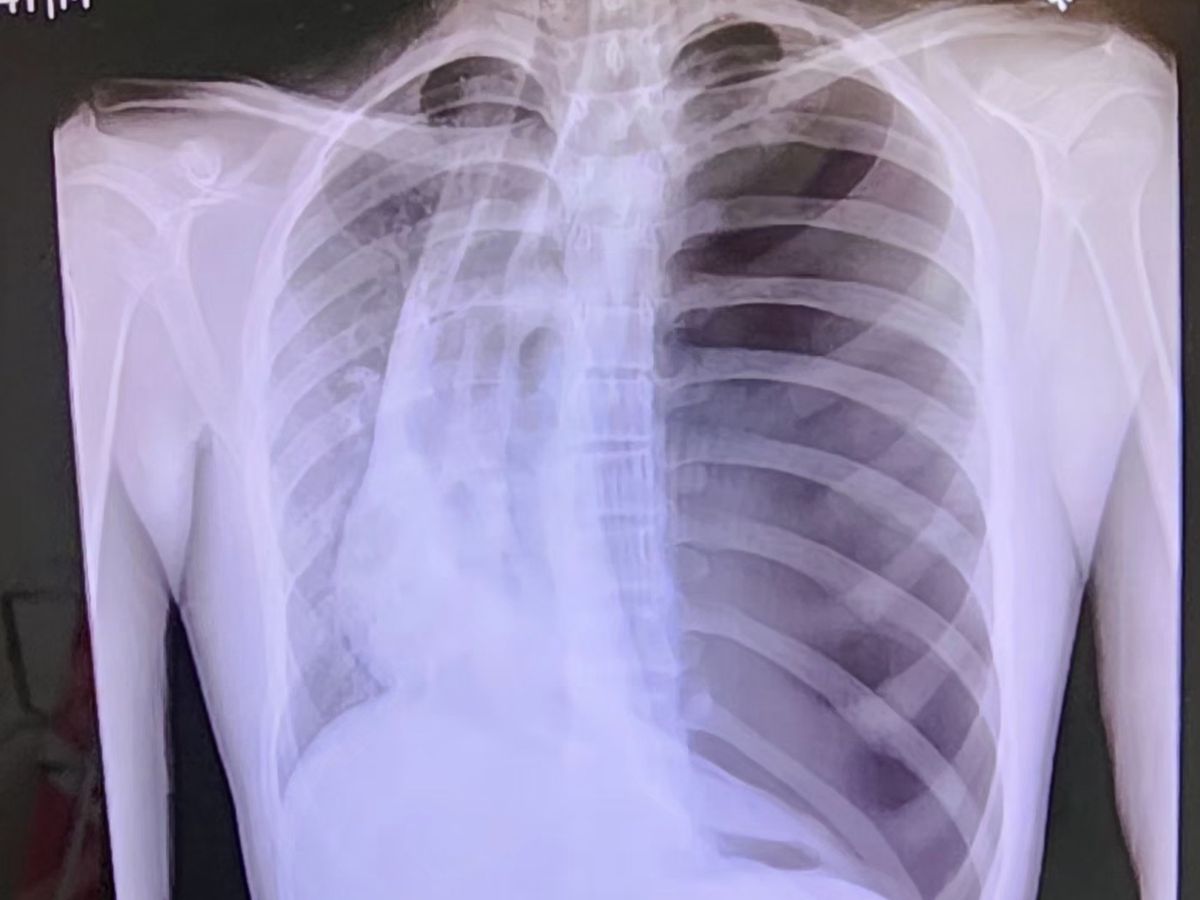

Hello, my name is Andy. I recently was hospitalized with a collapsed lung. I'm 14, a freshman at HISD. Anything will help with helping my family pay for any medical expenses not covered by insurance.

My doctor is planning a surgery to correct what's causing my lung to collapse this coming week. Thank you!